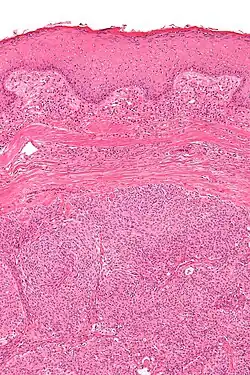

| Micrograph showing an acrospiroma. H&E stain. | |

Hidradenoma refers to a benign adnexal tumor of the apical sweat gland.[1][2] These are 1–3 cm translucent blue cystic nodules. It usually presents as a single, small skin-colored lesion, and may be considered closely related to or a variant of poromas.[3] Hidradenomas are often sub-classified based on subtle histologic differences, for example:[4]